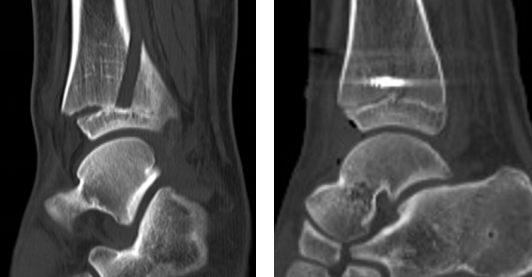

赵亮医生先为患儿进行相关检查,发现其左胫骨远端骨质断裂,累及内踝、前踝,骨骺受累。骨骺是人体身高长高、骨骼发育的重要解剖部分,赵医生建议行关节镜下微创手术治疗,该术式创伤小,而且踝关节镜手术操作简便,仅需2个0.5cm切口,手术时间短,术中出血少,术后2-3天患儿即可出院,回到课堂,手术的费用相对较低,对其家庭负担较小。

第二天,业务院长石荣剑、曹广超主任、赵亮主治医师手术团队为患儿进行了“关节镜下左踝关节滑膜清理+胫骨骨折复位内固定术”,手术取2个切口,关节镜进入关节腔内,见关节内滑膜增生,部分呈絮样悬浮状,刨刀清理增生滑膜组织。探查见胫骨远端骨折累及前踝、内踝,骨骺分离,骨骺骨折,关节镜监视下,对骨骺予以保护,复位胫骨远端骨折端,螺钉固定断端。手术40分钟顺利结束。

术前CT(左图)术后CT(右图)